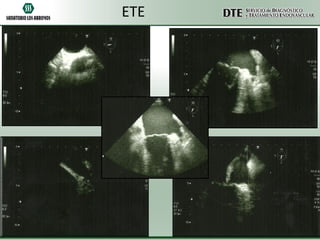

ETE

•Válvula mitral: normal

•Válvula aórtica: esclerosis leve.

•Válvula pulmonar: normal.

•Válvula tricúspidea: normal.

•No se detectaron alteraciones estructurales ni vegetaciones.

•Los septums interventricular e interauricular son nítido e íntegros.

•La raíz aórtica es de características normales.

•Las cavidades son de dimensiones y función normal.

•Se observan ambas orejuelas: ritmo irregular y su interior imagen

compatible con trombo.

•Ambas venas cavas se abocan normalmente en aurícula derecha.

•La aorta descendente examinada hasta el plano gástrico es normal.

Presenta un diámetro normal y la pared es normal.